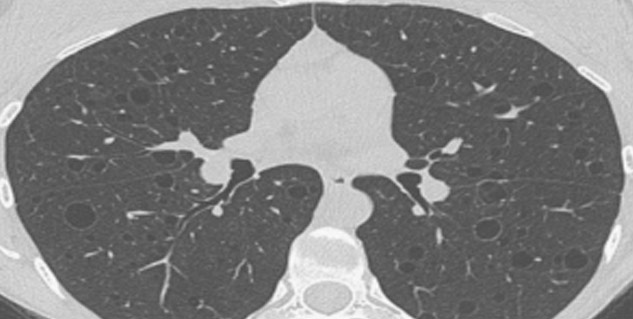

डॉक्टर अवधेश शर्मा के मुताबिक, एचआरसीटी एक्सरे का एडवांस फॉर्म होता है। इससे फेफड़ों की इमेजिंग की जाती है। कोरोना मरीजों में रोग की गंभीरता को जानने के लिए एचआरसीटी स्कैन यानी सीटी स्कैन किया जाता है।

डॉक्टर अवधेश शर्मा का कहना है कि कोरोना में देखा गया है कि ज्यादातर मरीजों में फेफड़े खराब होने लगते हैं। जिसकी वजह से मरीज को निमोनिया होने लगता है। अगर फेफड़ों के बाहरी तरफ निमोनिया मिल रहा है तो वह कोविड के फेवर में जाता है। फेफड़ों में राइट साइड में तीन लोब (lobe) होती हैं। लेफ्ट साइड का फेफड़े दो हिस्से में होते हैं। एक फेफड़े में 20 के करीब सेग्मेंट होते हैं। हर सेग्मेंट को डोपा स्कोर दिया जाता है। इससे कुल 40 का स्कोर हो जाता है।

डॉक्टर ने बताया कि सीटी स्कैन में देखा जाता है कि कौन सा फेफड़े का कौन सा लोब प्रभावित है। अगर फेफड़े को कोई नुकसान नहीं है तो शून्य स्कोर दिया जाता है। अगर 50 फीसद से कम है तो 1 स्कोर दिया जाता है। 50 फीसद से ज्यादा प्रभावित है तो 2 स्कोर दिया जाता है। 20 लोब में अगर सभी को 2 का स्कोर दे दिया तो कुल 40 स्कोर हो गए।

डॉक्टर ने उदाहरण देकर बताया कि अगर किसी कोरोना से प्रभावित पेशेंट के 10 सेग्मेंट्स का 50 फीसद से ज्यादा हिस्सा प्रभावित है तो स्कोर 20/40 (10x2=20) हो जाएगा। लेकिन अगर 10 सेग्मेंट 50 फीसद से कम प्रभावित हैं तो स्कोर 10/40 (10x1=10) होगा। डॉक्टर इस तरह से स्कोरिंग निकालते हैं। डॉक्टर अवधेश शर्मा का कहना है कि अगर पेशेंट में 40 में से 20 या उससे का स्कोर आता है तो निमोनिया ज्यादा गंभीर है। ऐसे पेशेंट ज्यादा गंभीर हालत में होते हैं।

एचआरसीटी को ही सीटी स्कैन कहा जाता है। फेफड़ों की जांच के लिए एचआरसीटी किया जाता है। डॉक्टर अवधेश शर्मा ने बताया कि जिन पेशेंट का आरटीपीसीआर नेगेटिव है लेकिन उनको लक्षण कोरोना के हैं। ऐसे पेशेंट को एचआरसीटी स्कैन कराना चाहिए। अगर ऐसे मरीजों में निमोनिया निकलता है तो उन मरीजों का इलाज कोरोना का ट्रीटमेंट ही होता है। डॉक्टर ने बताया कि आजकल जो निमोनिया हो रहा है वो कोरोना की वजह से हो रहा है। इसलिए टेस्ट में निमोनिया के लक्षण आने के बाद भी कोरोना का इलाज ही किया जाता है।

एचआरसीटी की जरूरत तब भी पड़ती है जब पेशेंट को मालूम है कि उसे कोरोना है, लेकिन डॉक्टर गंभीरता को जांचना चाहते हैं तो उन्हें पेशेंट का एचआरसीटी स्कोर देखना पड़ता है। फेफड़े कितने खराब हुए हैं, यह जानकर मरीज का इलाज किया जाता है। सीटी स्कैन में अगर पेशेंट के फेफड़े 50 फीसद से ज्यादा खराब आ रहे हैं तो उस पेशेंट को गंभीर स्थिति वाले इलाज के लिए रेफर किया जाता है। अगर पेशेंट का सीटी स्कोर कम होता है उसके ठीक होने की संभावना ज्यादा होती है। रोग की गंभीरता जानने के लिए एचआरसीटी स्कैन किया जाता है।